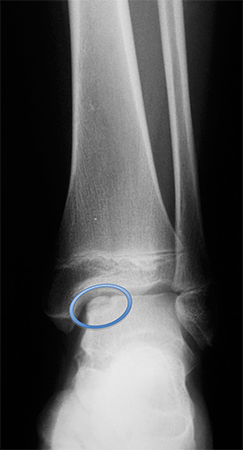

Stimulating the development of hyaline cartilage (autologous chondrocyte implantation, osteochondral allograft or autograft).[42] Each of these techniques has advantages and disadvantages. Studies have yet to show which salvage technique provides the best outcome.[Figure caption and citation for the preceding image starts]: Osteochondral lesion of medial talusFrom the collection of H. Chambers, MD [Citation ends].